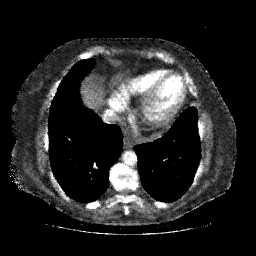

Generated VENOUS CT scan (A→B translation)

No window - Raw intensity values

Lung window (WL -600, WW 1500 β†’ Low βˆ’1350, High +150)

Mediastinum window (WL 40, WW 400 β†’ Low βˆ’160, High +240)